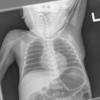

Normal neonate

Date: 02/07/2010

Views: 6048